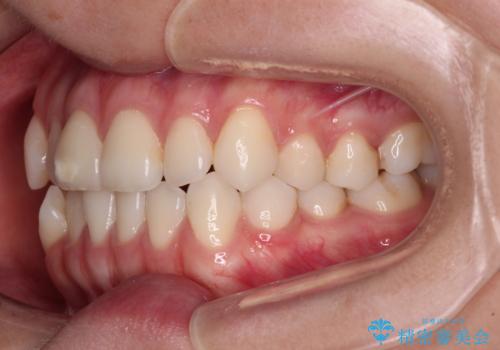

- 前歯のデコボコと奥歯の咬み合わせを気にして来院された患者様です。

右側の奥歯は、上が外側に転位した鋏状咬合を呈しており、前歯のデコボコ改善と並行して咬み合わせを改善していく必要がありました。

装置はワイヤー装置でもインビザラインのマウスピースでもどちらでも適用でしたが、自己管理の煩わしさを嫌い、ワイヤー矯正にて治療を行うこととしました。

ワイヤー矯正を選択されたため、鋏状咬合を確実に改善するために補助装置を併用することとしました。